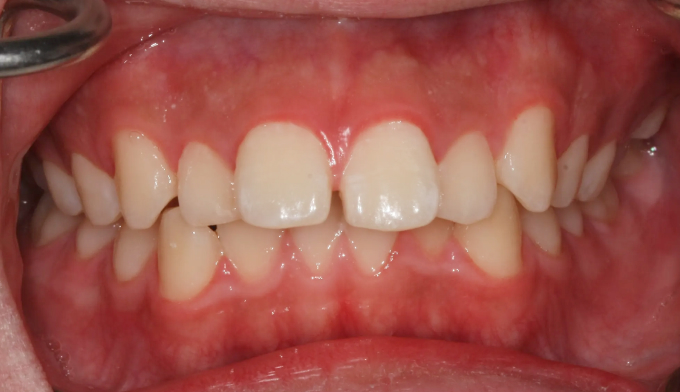

덧니,

돌출입

10대

2025.02.11